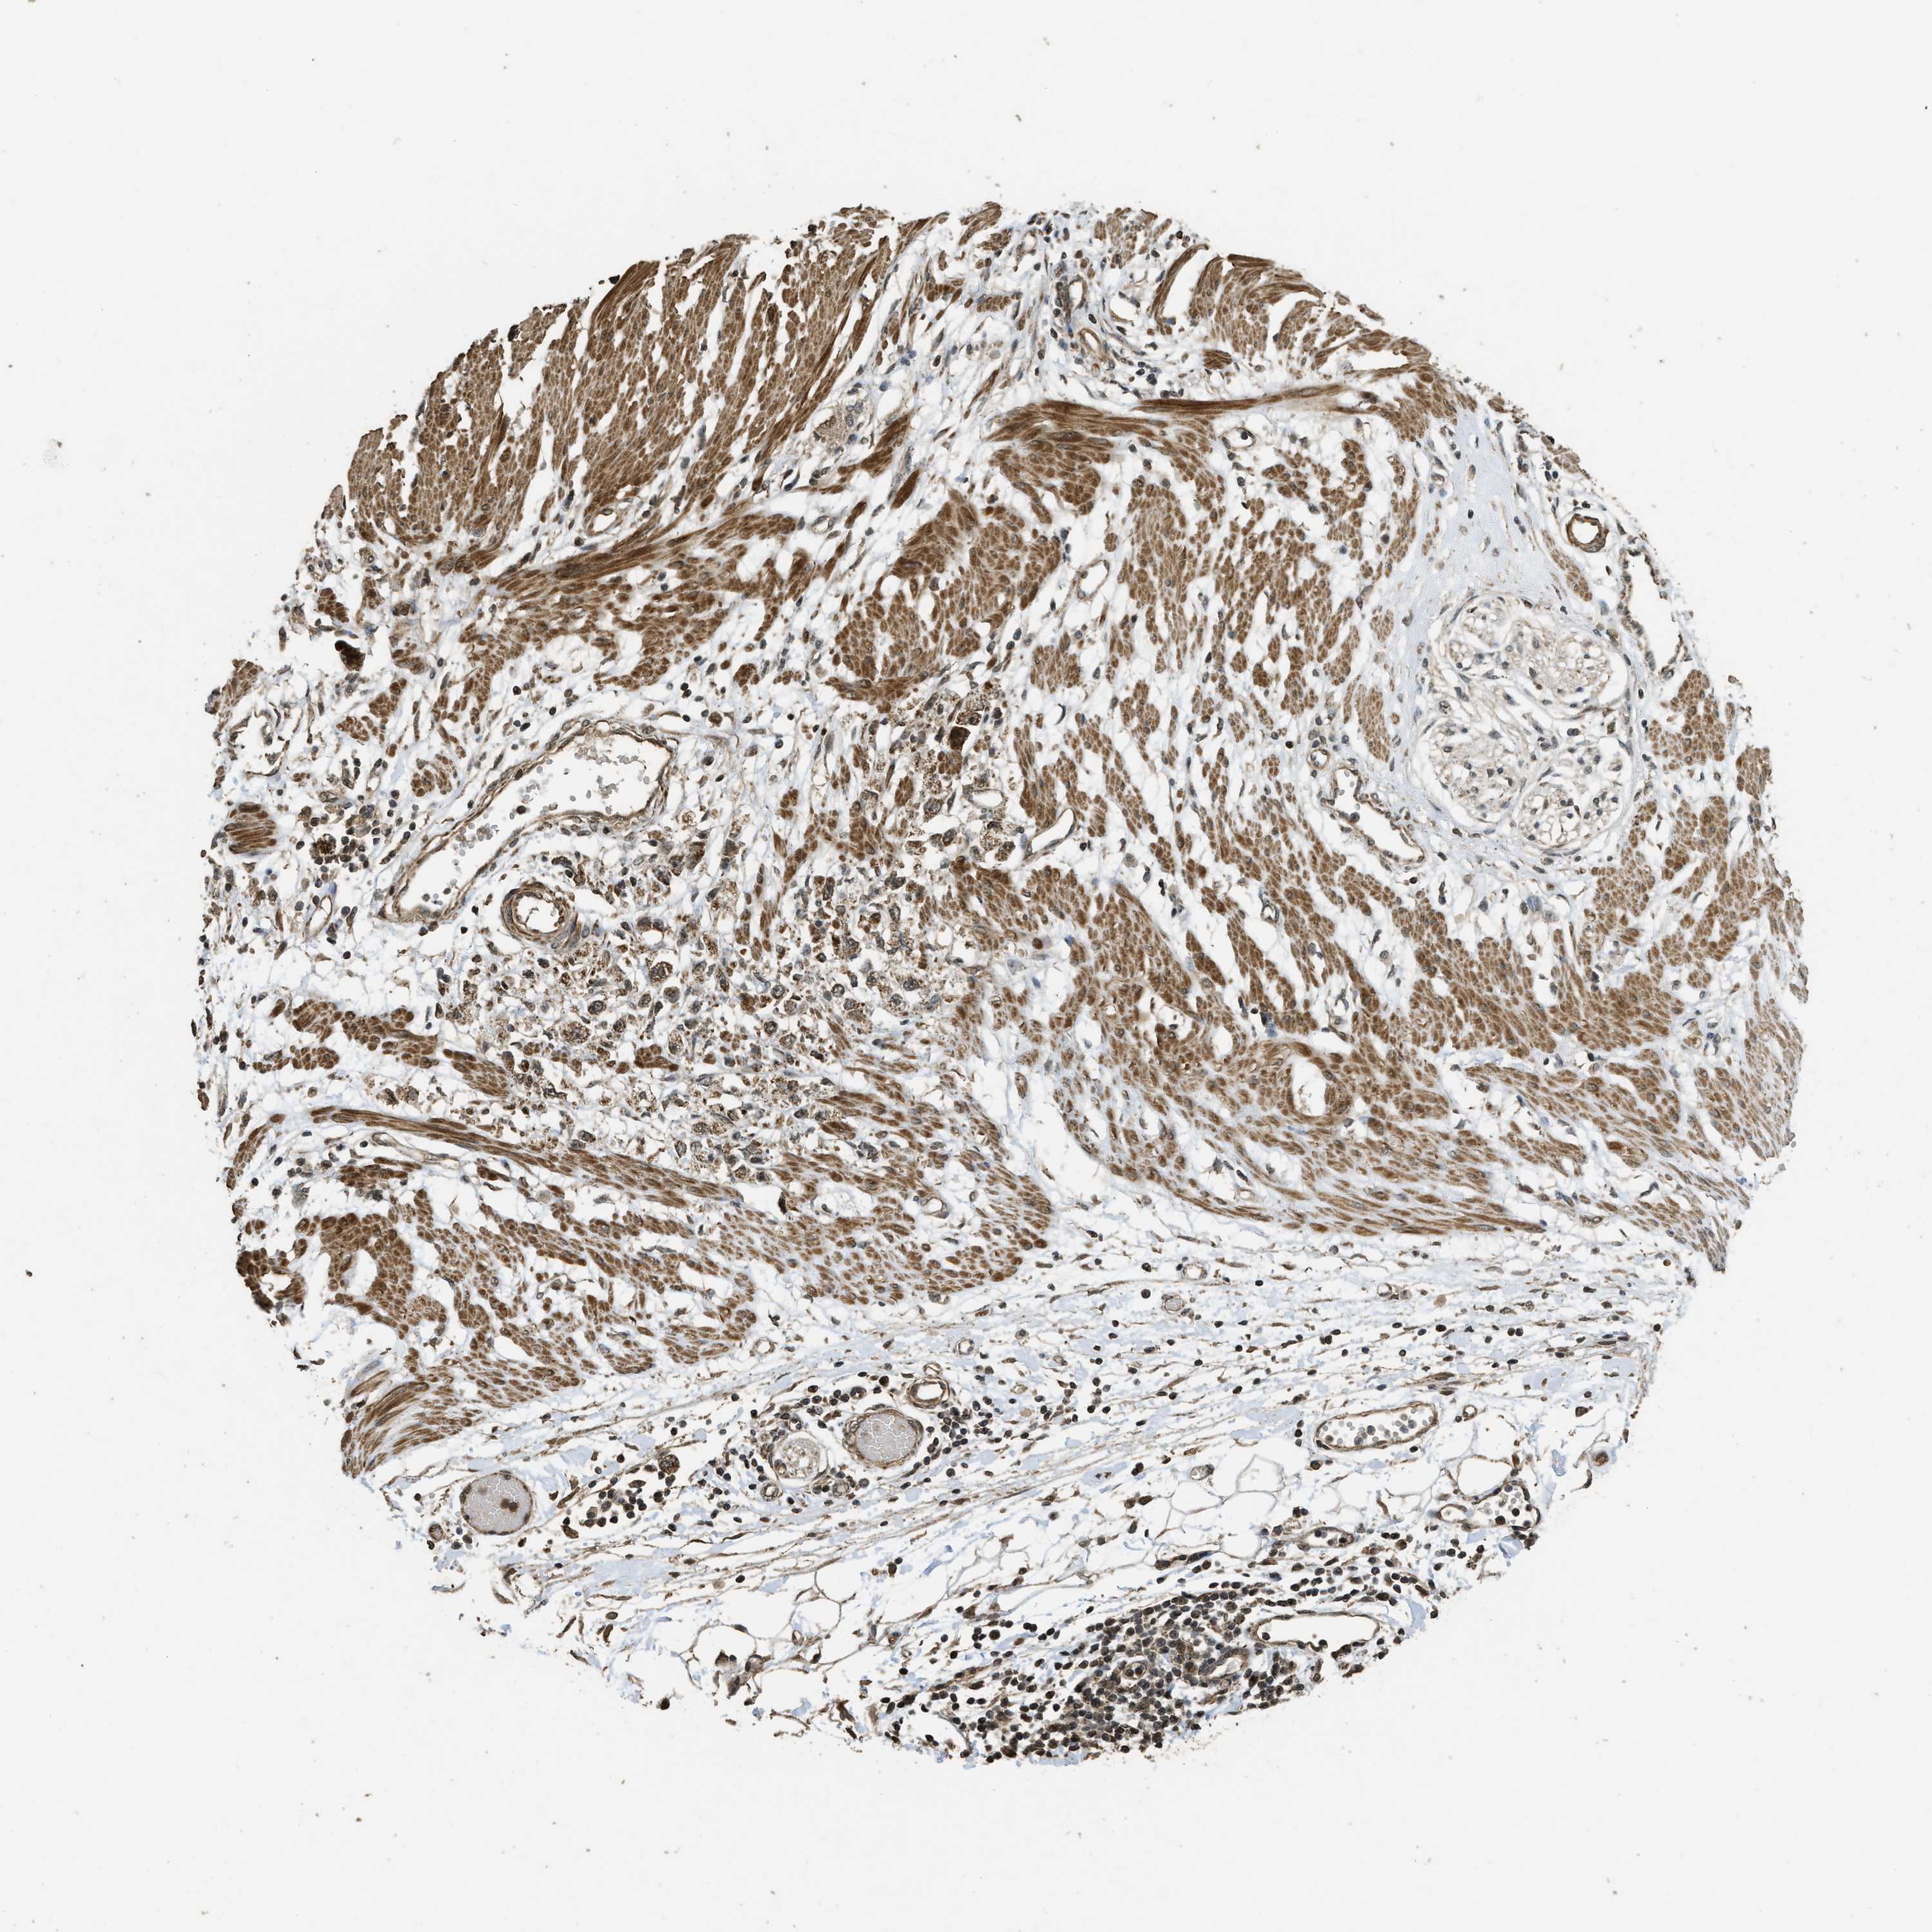

STOMACH CANCER - Protein expressioni

A mouse-over function shows sample information and annotation data. Click on an image to view it in a full screen mode. Samples can be filtered based on level of antibody staining by selecting one or several of the following categories: high, medium, low and not detected. The assay and annotation is described here.

Note that samples used for immunohistochemistry by the Human Protein Atlas do not correspond to samples in the TCGA dataset.

Antibody stainingi

Antibody staining in the annotated cell types in the current human tissue is reported as not detected, low, medium, or high, based on conventional immunohistochemistry profiling in selected tissues. This score is based on the combination of the staining intensity and fraction of stained cells.

Each image is clickable and will lead to virtual microscopy that enables deeper exploration of all samples and also displays staining intensity scores, fraction scores and subcellular localization as well as patient and tissue information for each sample.

Antibody HPA051322

Antibody CAB017111

Staining

High

Medium

Low

Not detected

Intensity

Strong

Moderate

Weak

Negative

Quantity

>75%

75%-25%

<25%

None

Location

Nuclear

Cytoplasmic/membranous

Cytoplasmic/membranous,nuclear

Adenocarcinoma, NOS

Adenocarcinoma, High grade